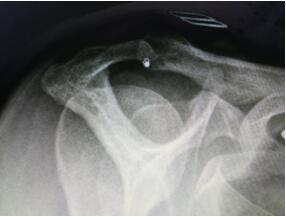

???????????????????X片檢查發(fā)現(xiàn)患者為三型肩峰